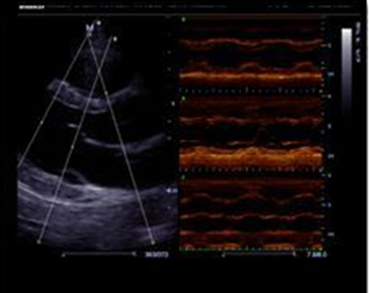

Free Xros M

Выполнение точных анатомических измерений посредством свободного размещения линий М-режима под любым углом. Повышение информативности исследования достигается с помощью одновременного использования до 3 линий М-режима.